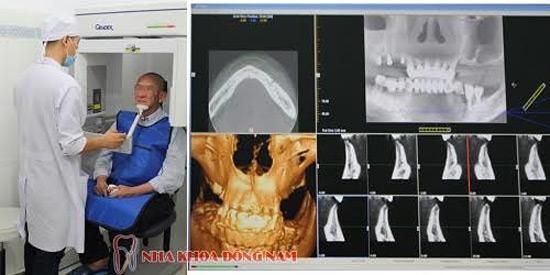

Bước 2: Chụp phim CT 3D phân tích xương hàm

Tại Nha Khoa Đông Nam, bệnh nhân sẽ được chụp phim CT 3D Scanner phân tích xương hàm miễn phí tại chỗ. Từ những tấm phim 3D này sẽ giúp bác sĩ hiểu rõ hơn cấu trúc của xương hàm, từ đó mới đưa ra những giải pháp điều trị cụ thể, lựa chọn được kích thước Implant ETK Active sao cho phù hợp với mật độ xương hàm của bệnh nhân.

Chụp phim CT 3D miễn phí để phân tích xương hàm